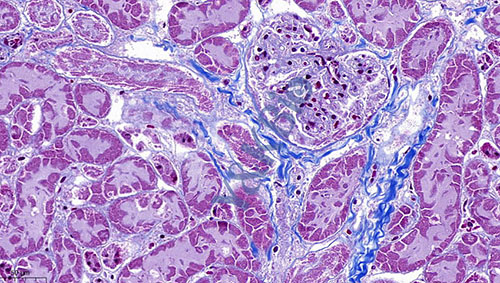

云南Masson染色是病理染色服务中比较常见的一种,Masson染色用于胶原纤维和肌纤维的染色及鉴定;染色结果:胶原纤维呈蓝色、肌纤维呈红色、细胞核呈蓝黑色。